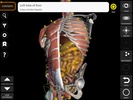

Nama Paket | com.catfishanimationstudio.MuscularSystemLite |

| Kategori | Edukasi & Bahasa | |

| Penerbit | Catfish Animation Studio | |

| Unduhan | 64,203 | |